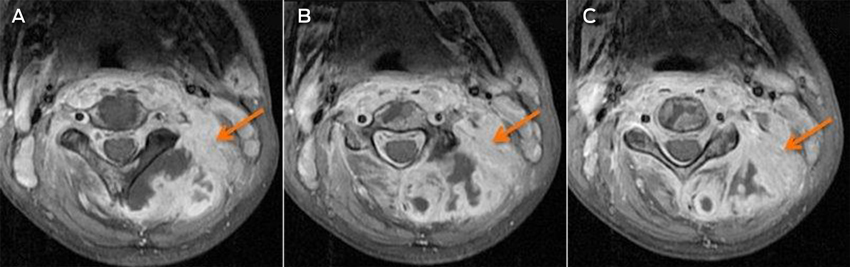

A magnetic resonance imaging scan on Day 7 identified an infiltrative lesion in the posterior paravertebral muscles, involving cervical vertebrae 1–5 and the spinal canal at that level (Box). The diagnostic possibilities were primary or secondary malignancy or infection. A pleural tap the next day drained 500 mL of blood-stained fluid. Laboratory results confirmed an empyema that grew S. aureus from the tap fluid.